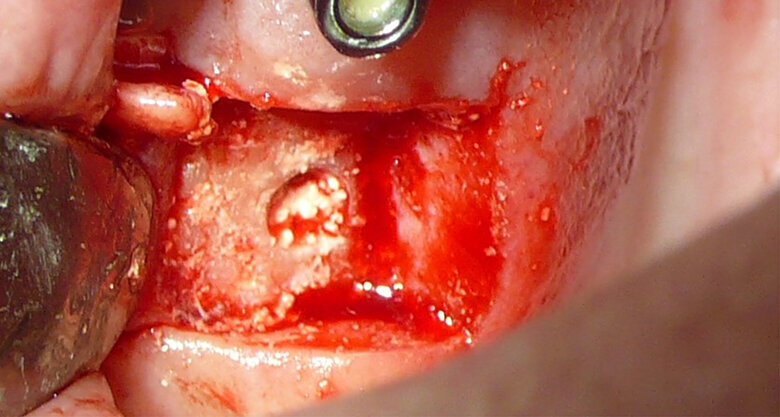

A randomised clinical study was conducted on 128 patients. 101 patients with less than 4mm subantral crest- height underwent a uni- or bilateral transcrestal hydrodynamic ultrasound Piezotome sinus lift (INTRALIFT) with four different and randomly allocated bone graft materials (mono- or biphasic mouldable and self-hardening biomaterial, granular synthetic and xenogeneic bone substitute) in 114 INTRALIFT sites. The transcrestal Piezotome INTRALIFT provides the least risk of mem- brane-perforations and has proven to detach the periosteum of the sinus membrane cleanly from the bony base of the antrum, thus preventing biases of the study already at the stage of the surgery. The clean detachment of the periosteum from the bone base does not interfere with the regular bone regeneration in the subantral scaffold by dissection or lacerations of the periosteal layer of the sinus membrane, which carries the pre-osteoblast cell layer.10–15

Figure 1 shows a split-mouth case with a bilateral INTRALIFT procedure: after a small crestal “booklet”-flap of approx. 7x7mm is detached, the sinus floor is safely opened with ultrasound Piezotome tips (Figs. 2 & 3), the sinus membrane then detached by the hydrodynamic cavitation effect of the Piezotome-tip TKW5 plugged into the approach canal (Figs. 4 & 5) and the subantral scaffold filled with 2cm of randomly assigned biomaterial (Figs. 6 & 7), followed by wound closure (Fig. 8). After a mean healing period of 8,4 months X-Mind trium CBCT scans were performed, the digital setup of the future bridge constructed with the AIS 3D app and the bone density determined in the sinus-lift site around a virtual implant (Fig. 9). Standardised implants (4mm in diameter and 12mm in length) were then inserted in the position of the virtual implant and insertion torque values (ITV) measured intra-surgically (test groups; Fig. 10). A total of 27 patients with sufficient native subantral crestal bone (min. crest width: 6 mm, height: 12 mm) were screened by X-Mind trium CBCT for bone density with the virtual implant (Fig. 11), the standardised implant inserted and the ITV recorded (control group). Figure 12 depicts the final result after implant insertion in the patient case shown in Figures 1–9.